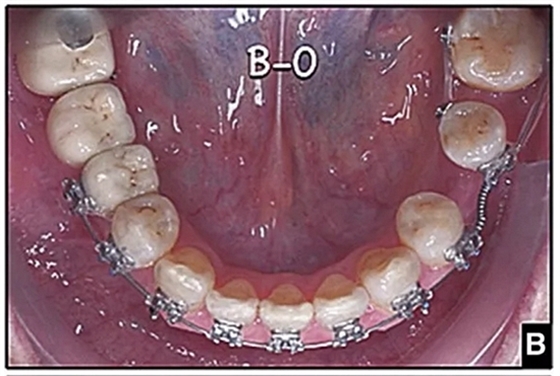

圖15.A,去除固定裝置一個月后,下頜左側第二前磨牙復發(fā),移動到種植體愈合的部位; B,B-0表示開始再治療,通過鏈圈和推簧的矯正復發(fā); C,B-9是治療結束后3個月回訪時下頜弓的咬合面觀,這是再治療階段的9個月。下頜左側第二前磨牙和第三磨牙的頰面粘合一個固定保持器,以防止復發(fā)。

完全固定的Damon Q設備(加利福尼亞州Glendora的Ormco)與制造商指定的弓絲和附件一起使用。下頜弓,一開始放入0.014英寸的鎳鈦弓絲,5個月后放入0.014×0.025英寸的鎳鈦弓絲。舌側扣和鏈圈放置在下頜尖牙和第二前磨牙上以控制扭轉。在治療的第7個月,將下頜弓絲換成0.017× 0.025英寸的β鈦絲。另一個舌側扣和鏈圈放置在下頜左側第三磨牙上以提供近中牽引力(圖9)。在16個月的治療結束時,所有的扭轉都得到了矯正,缺牙間隙縮小到8 mm(圖8),但由于頰側骨板的嚴重吸收,牙槽嵴的寬度仍然很窄(約3 mm)(圖9)。通過正畸移動下頜左側第二前磨牙,在前磨牙之間產(chǎn)生一個種植部位。在第一和第二前磨牙之間的弓絲上放置一個推簧,并將舌側扣和鏈圈放置在第一前磨牙和第三磨牙之間(圖9),在頰側和舌側施加力。施力均為輕力,每個表面上約2盎司(28.3 cN)以控制牙根側面的吸收。

經(jīng)過32個月的活動治療后,上下牙弓排齊良好,下頜第一磨牙區(qū)的雙側牙間隙可用于種植(圖12,A和13,A)。